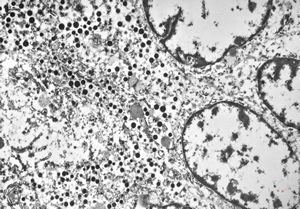

F,41y. | synovial metaplasia - capsule of implantate